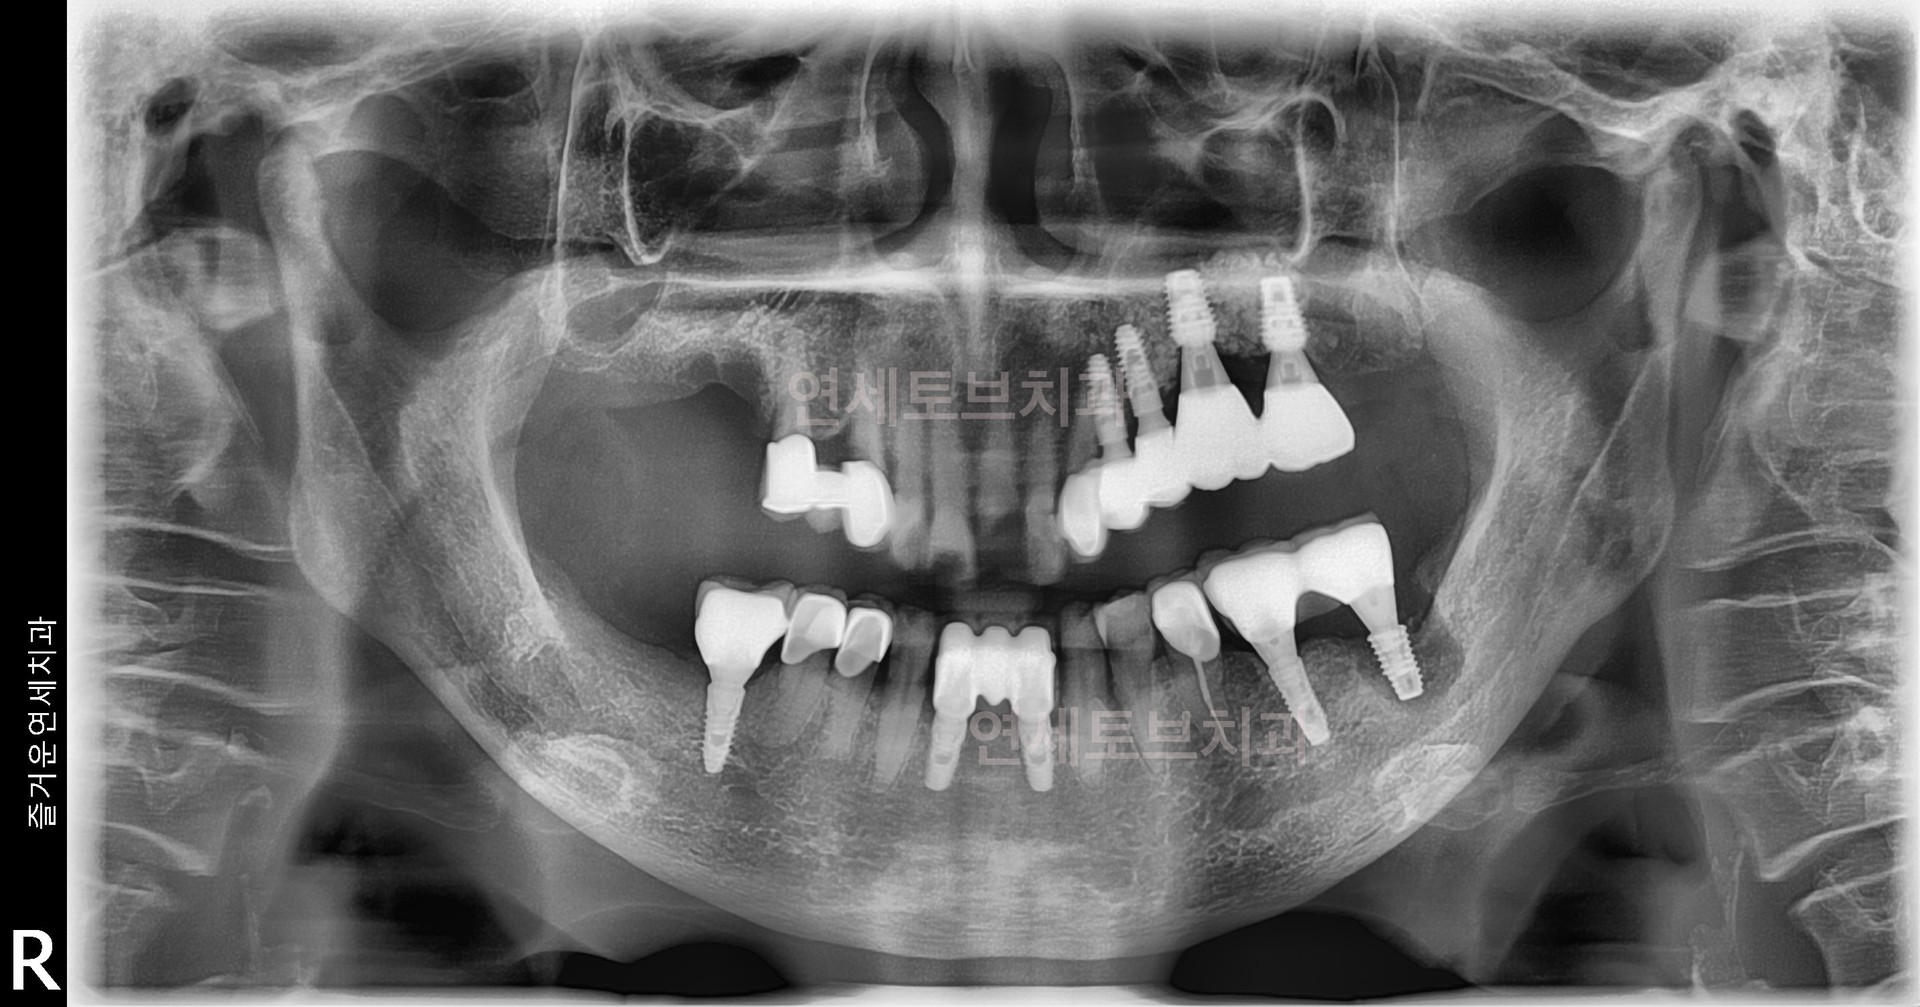

기존에 식립한 임플란트에 문제가 발생했을 때 이를 다시 치료하거나 교체하는 과정을 말합니다.

임플란트는 반영구적으로 사용할 수 있지만, 다양한 원인(잇몸뼈 흡수, 임플란트 주위염, 보철물 파손, 식립 위치 오류 등)으로 인해 재치료가 필요할 수 있습니다

기존에 식립한 임플란트에 문제가 발생했을 때 이를 다시 치료하거나 교체하는 과정을 말합니다. 임플란트는 반영구적으로 사용할 수 있지만, 다양한 원인(잇몸뼈 흡수, 임플란트 주위염, 보철물 파손, 식립 위치 오류 등)으로 인해 재치료가 필요할 수 있습니다